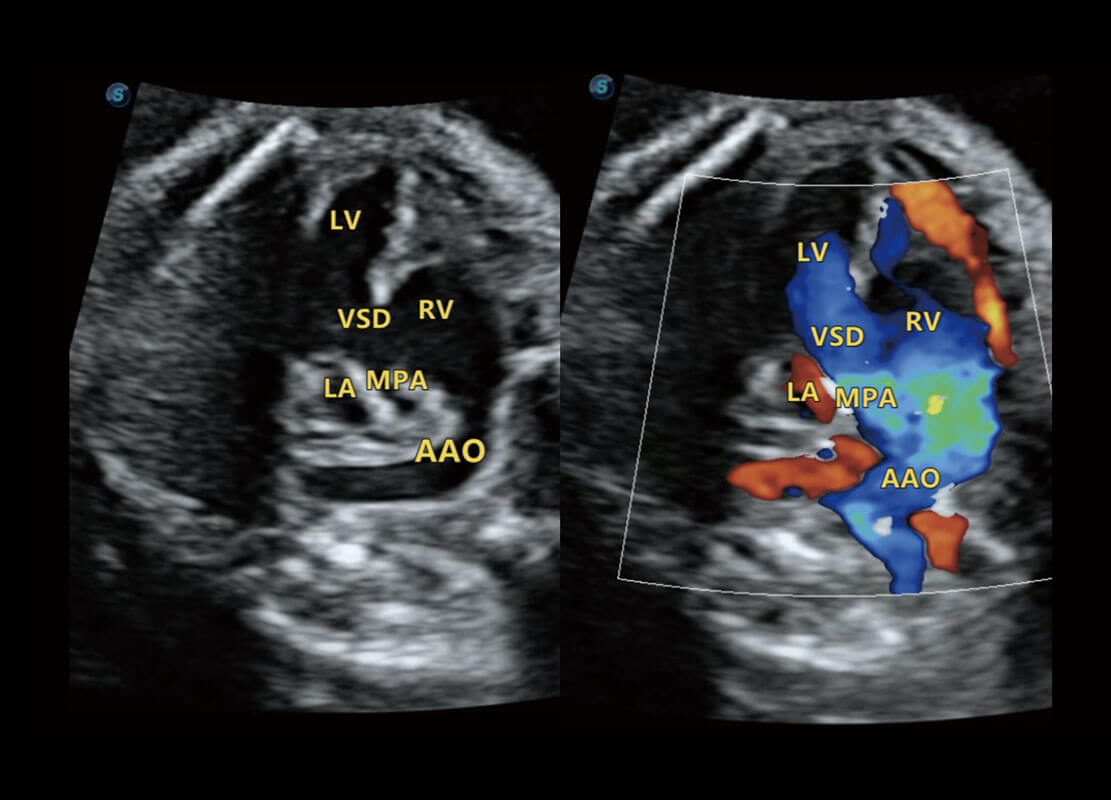

P60搭載一系列胎兒心臟成像技術(shù),實現(xiàn)精細的胎兒心臟評估。

四腔切面

四腔心血流

右室雙出口

胎心容積成像